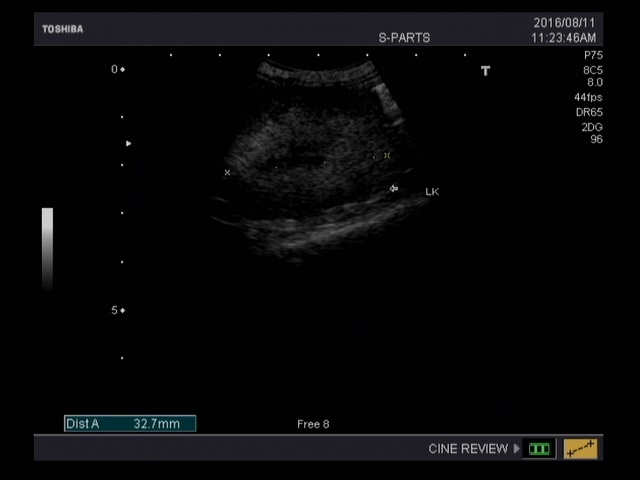

送到醫院做了血檢,發現阿花是慢性腎臟衰竭還嚴重脫水,當天驗出血中尿素跟肌酸酐都超標,後來給了幾天點滴後血紅素卻下降到10%以下而開始不吃不喝。當下就決定讓阿花輸血,同時放了食道胃管替阿花灌食,希望在透過治療後,也能像一般腎貓出院,繼續維持貓咪的生活品質。

在我能力範圍,我想要給浪貓的不只食物,更有機會是是醫療及後續的生活品質。期待大家的幫忙。動物近況說明: 8/23

從送阿花到恩澤到目前十多天,每天大致上阿花就是給點滴跟灌食,中間經歷了一次輸血,因為血紅素過低,輸完一次之後就只能靠點滴維生,嘗試移開點滴後腎臟的功能仍然很差無法恢復,在8/23這天去當小天使了,謝謝大家關心跟醫師的盡力,醫藥費部分請大家幫忙,感謝!!